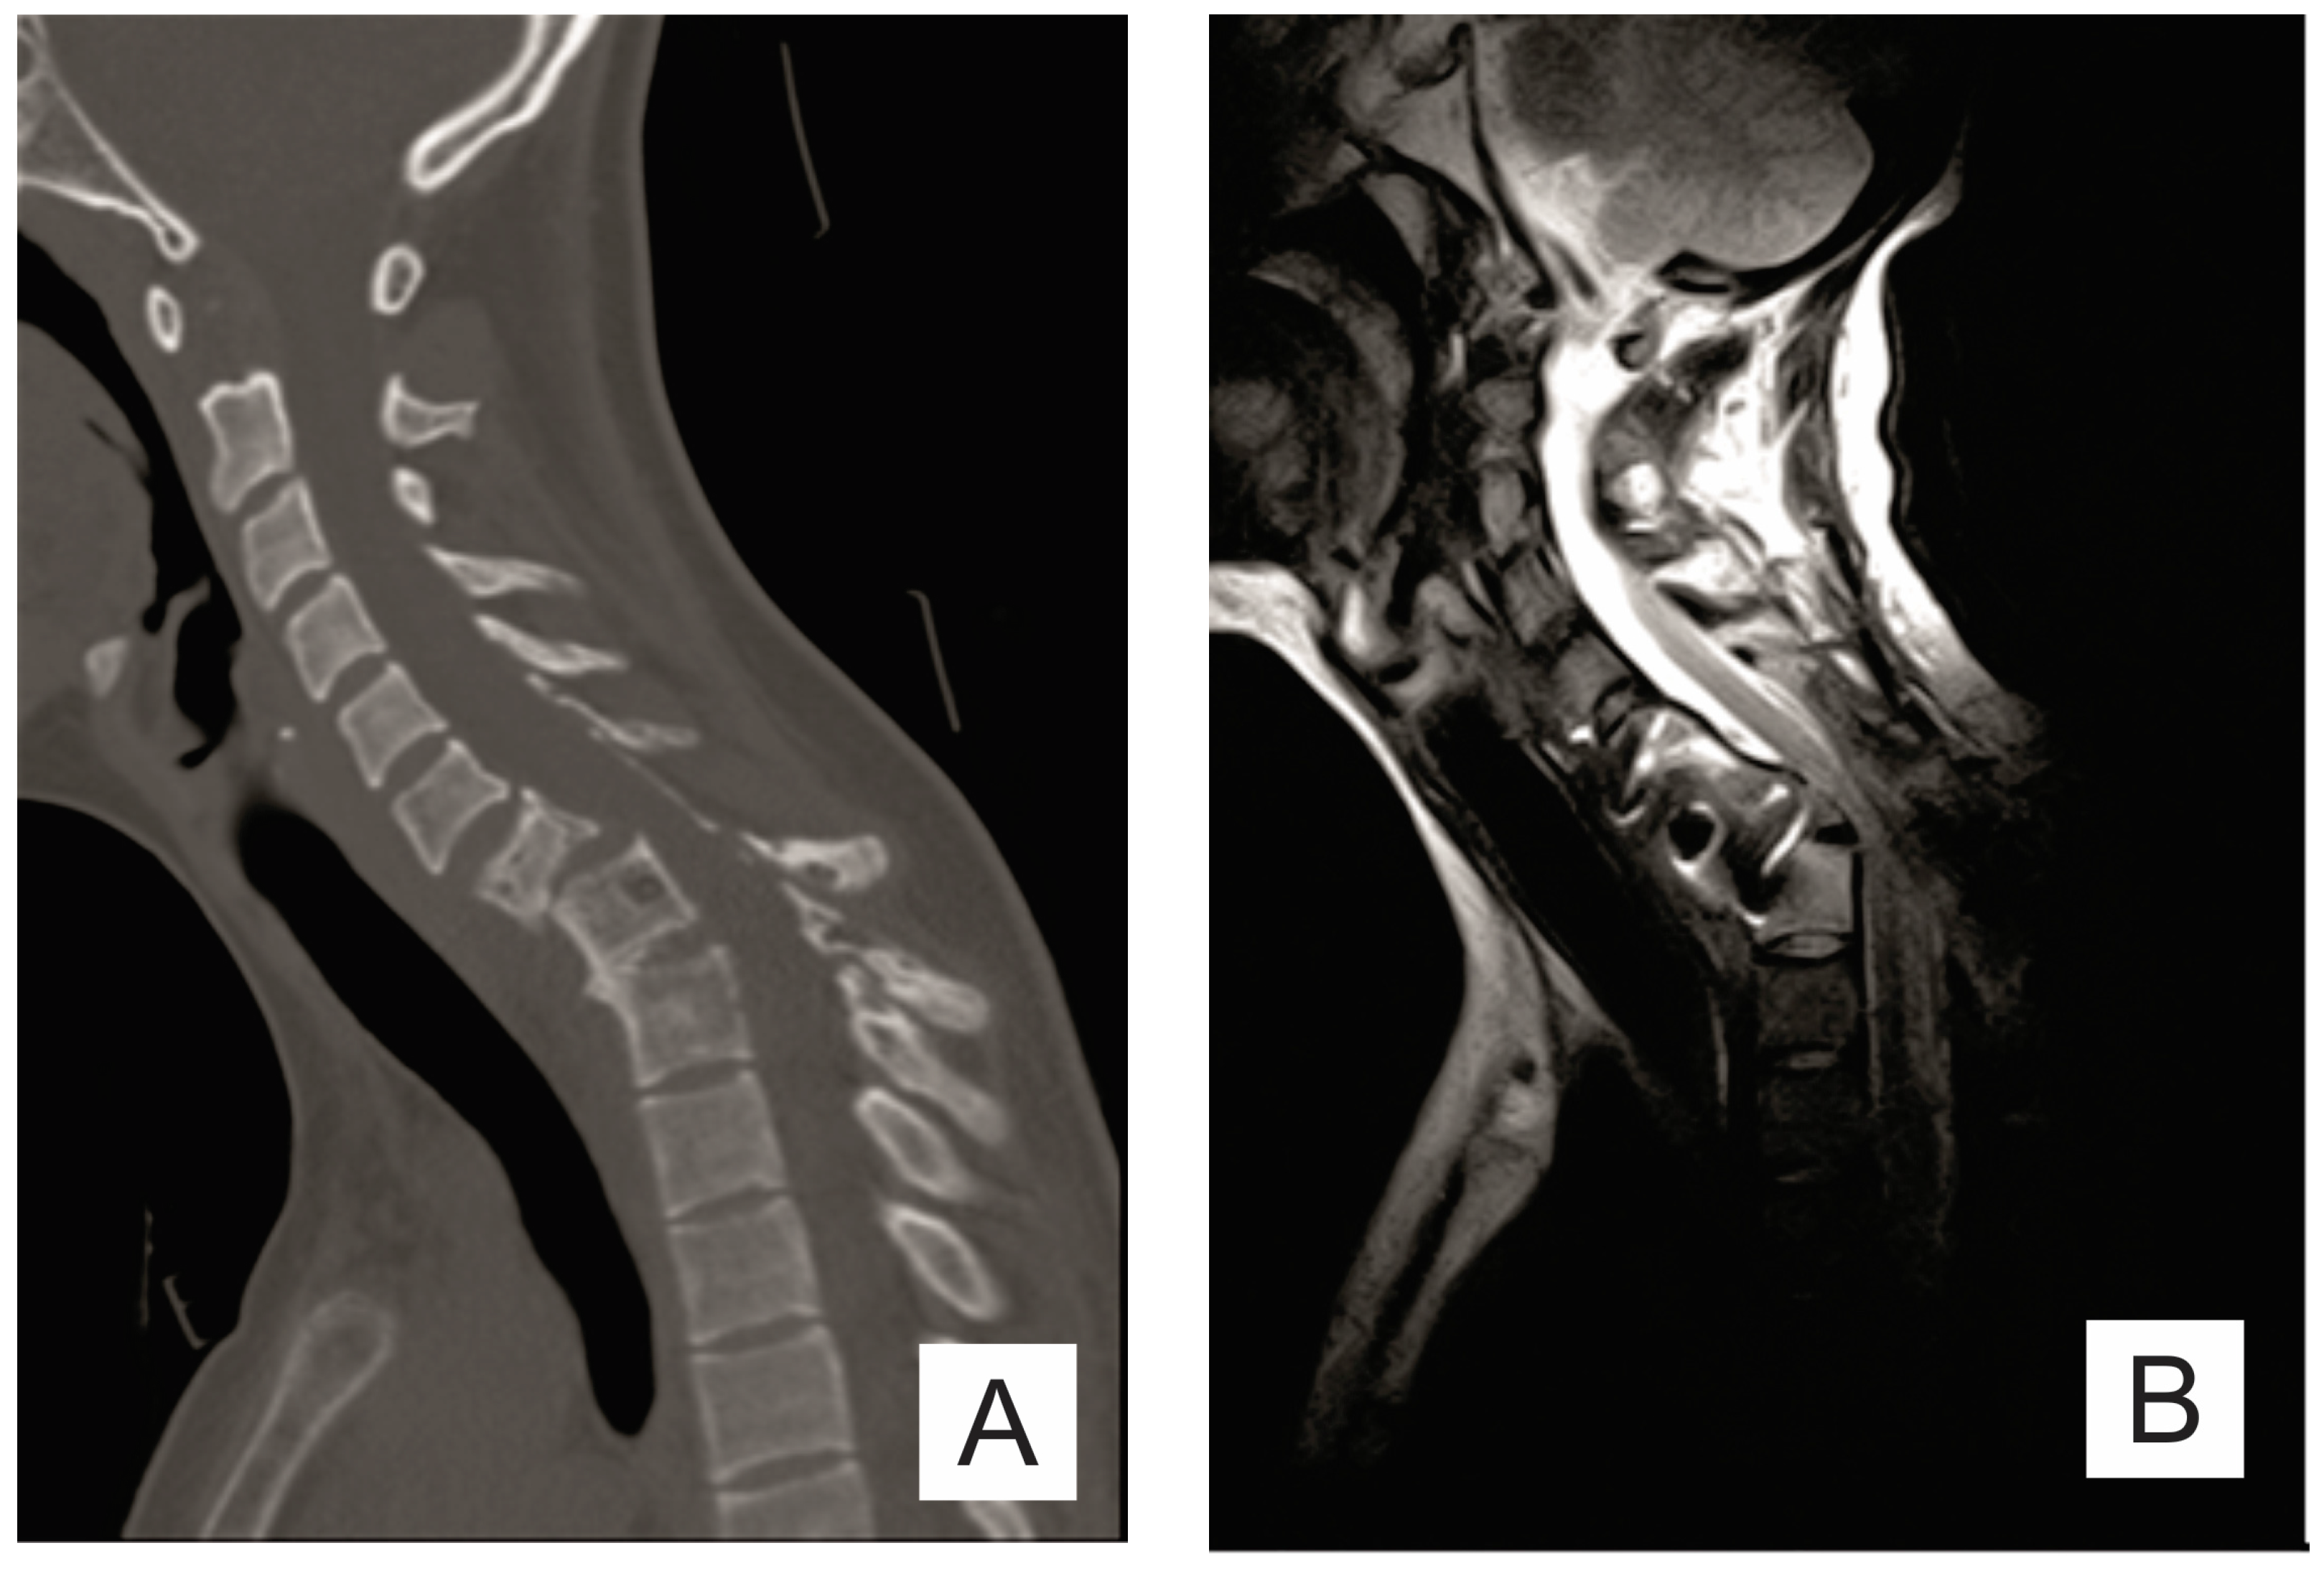

2. Case Report